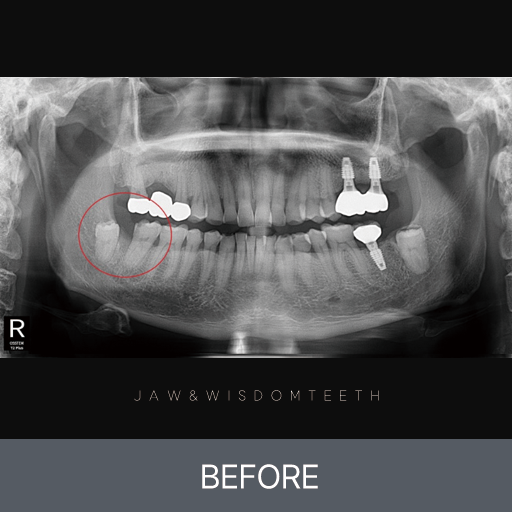

사랑니 CASE